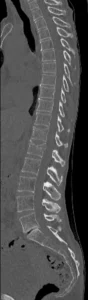

Tomografia Computada

TC ventanas de partes blandas y óseas. MPR en planos coronal y sagital. Permite caracterizar mejor la fractura, confirmar la protrusión del muro posterior hacia el canal. Descartar hematomas epidural y paravertebral.